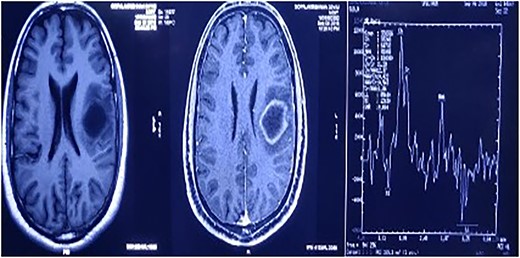

MRI brain with contrast revealed a heterogeneous irregular rim of an enhancing lesion with a size of 3.6 × 3.4 × 2.4 cm appearing in the left frontal subcortical region, with mild perilesional edema extending into the corona radiata and external capsule (Fig. 1). Due to an increased intracranial pressure, there was a mild midline shift of 5.3 mm toward the right side. Moreover, there was no evidence of intralesional hemorrhage or calcification seen.

MRI brain with contrast—a heterogeneous irregular rim of an enhancing lesion with a size of 3.6 × 3.4 × 2.4 cm appearing in the left frontal subcortical region, with mild perilesional edema extending into the corona radiata and external capsule.

A magnetic resonance spectroscopy (MRS) was performed and revealed an increased choline, considered as a marker of neoplasms, reduced NAA, and prominent lipid/lactate peaks. (Ch/NAA-4.0) (Ch/Cr-1.7) (Fig. 2).

MRS showed an increased choline, reduced NAA, and prominent lipid/lactate peaks; (Ch/NAA-4.0) (Ch/Cr-1.7).